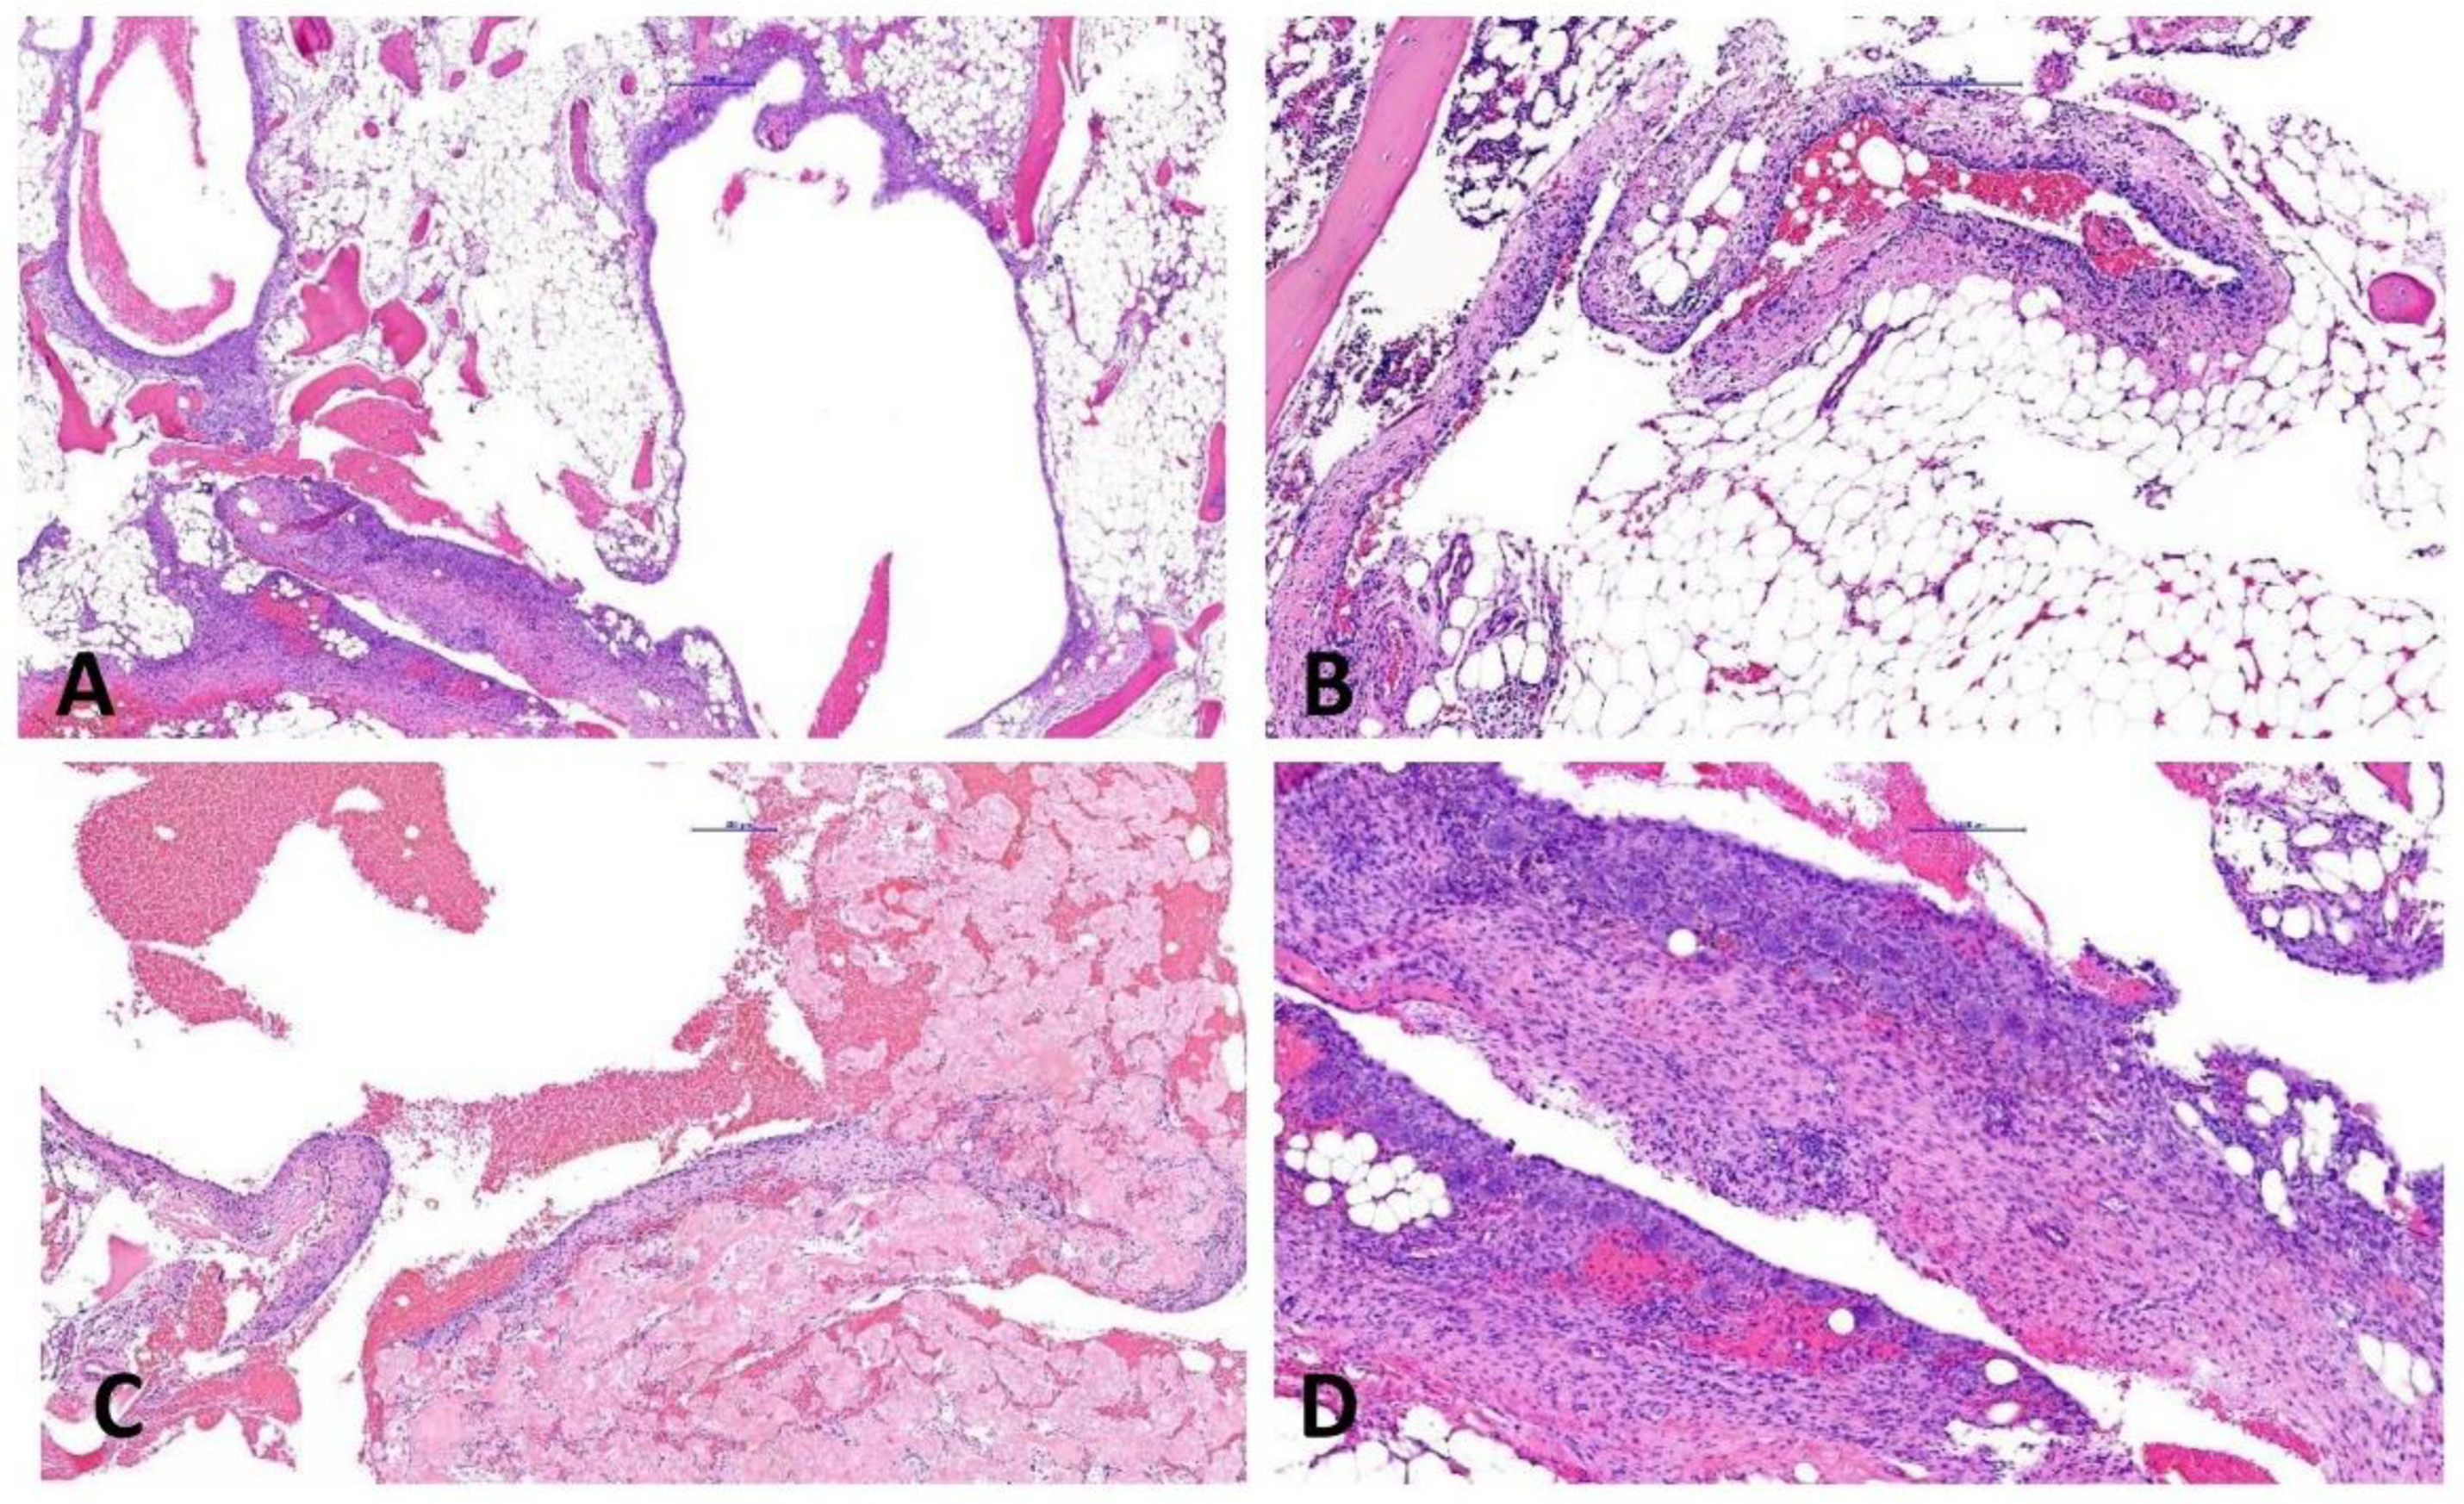

2.2. Complex Cystic Bone Lesions (Cases #2 & 3)

2.3. EWSR1::NFATC2-Rearranged Soft Tissue Sarcoma (Case #4)

2.4. EWSR1::NFATC2-Rearranged Bone Sarcoma (Case #5)